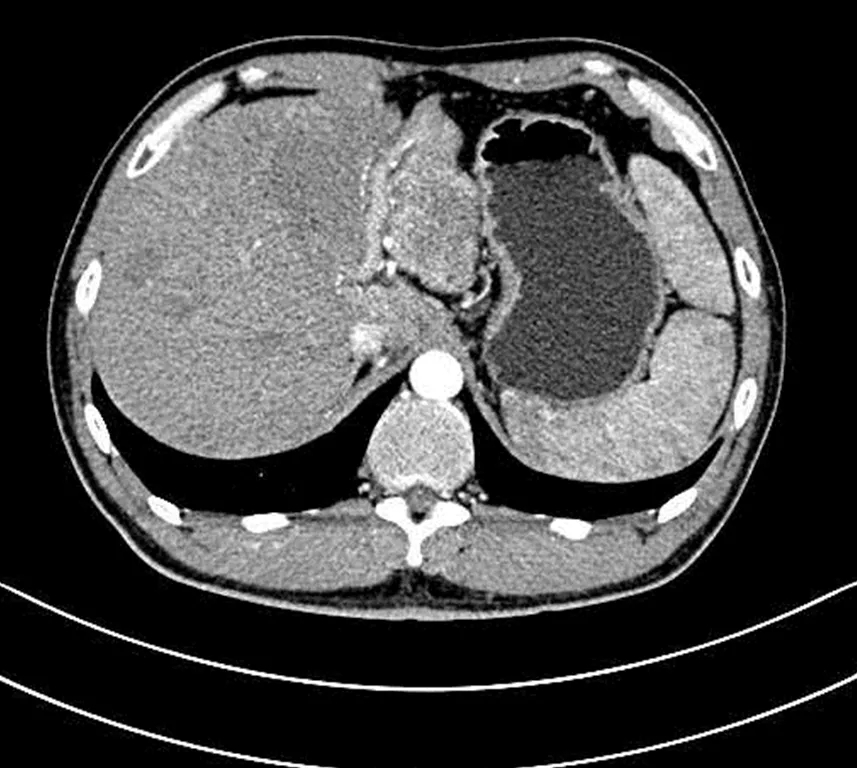

该病例为一名34岁多发巨块型肝癌患者,肝内见一个巨大肿瘤病灶及多发转移病灶。肝内巨大病灶压迫胃部,导致患者进食差,少许进食即饱腹感明显,腹痛,生活质量差。

阳西总医院人民医院肿瘤科成功为患者进行了肝动脉灌注化疗(HAIC)。HAIC疗法经股动脉将微导管置于肝肿瘤分支血管,通过微导管将抗肿瘤药物直接送达肝内肿瘤血管达到治疗目的。经过1个周期的治疗,患者肝部肿瘤较前明显缩小,对胃的压迫减轻,已能正常进食,腹痛腹胀消失,再经过2个周期的HAIC治疗后,肝内巨大肿瘤染色基本消退。